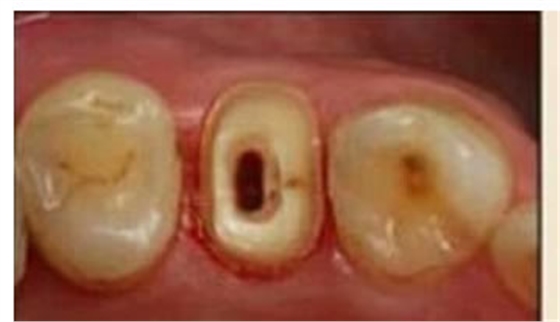

圖3:根管內(nèi)殘留物

圖4:超聲去除根管殘留物。

根管壁殘留物的存在直接影響著纖維樁的粘接和固位,是纖維樁脫落的主要原因之一。由于圓形的根管鉆和根管形態(tài)不完全一致,終鉆預(yù)備完成后大多情況下樁道側(cè)壁會(huì)有不同程度的牙膠和封閉劑等殘留物附著(圖 3)。因此,建議X線檢查根管預(yù)備情況,選用超聲潔牙機(jī)更換較細(xì)工作尖進(jìn)入根管,徹底去除樁道根管壁上附著的殘留物(圖4)。使用根管銼去除殘留物時(shí),很難清除干凈;禁止使用牙膠溶劑如丁克除、氯仿等有機(jī)溶劑去除殘留物,以免破壞根尖區(qū)牙膠的封閉,或有機(jī)溶劑粘附于根管壁形成蠟?zāi)ざ绊懻辰印?/p>